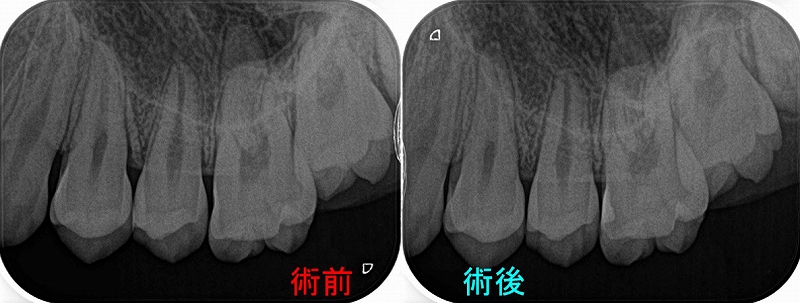

レントゲン

第二大臼歯に直接覆髄がしてありますが、根の方には大きな透過像(骨が溶けている場所)

第一大臼歯遠心根にもうっすら透過像あり。

今回のケースは珍しくフィステル(膿の出口)が2か所あります。

ということは膿の原因場所が2か所あると推測されます。

第一大臼歯はそんなに問題無いように見えるので、とりあえず第二大臼歯の治療を行うことにしました。